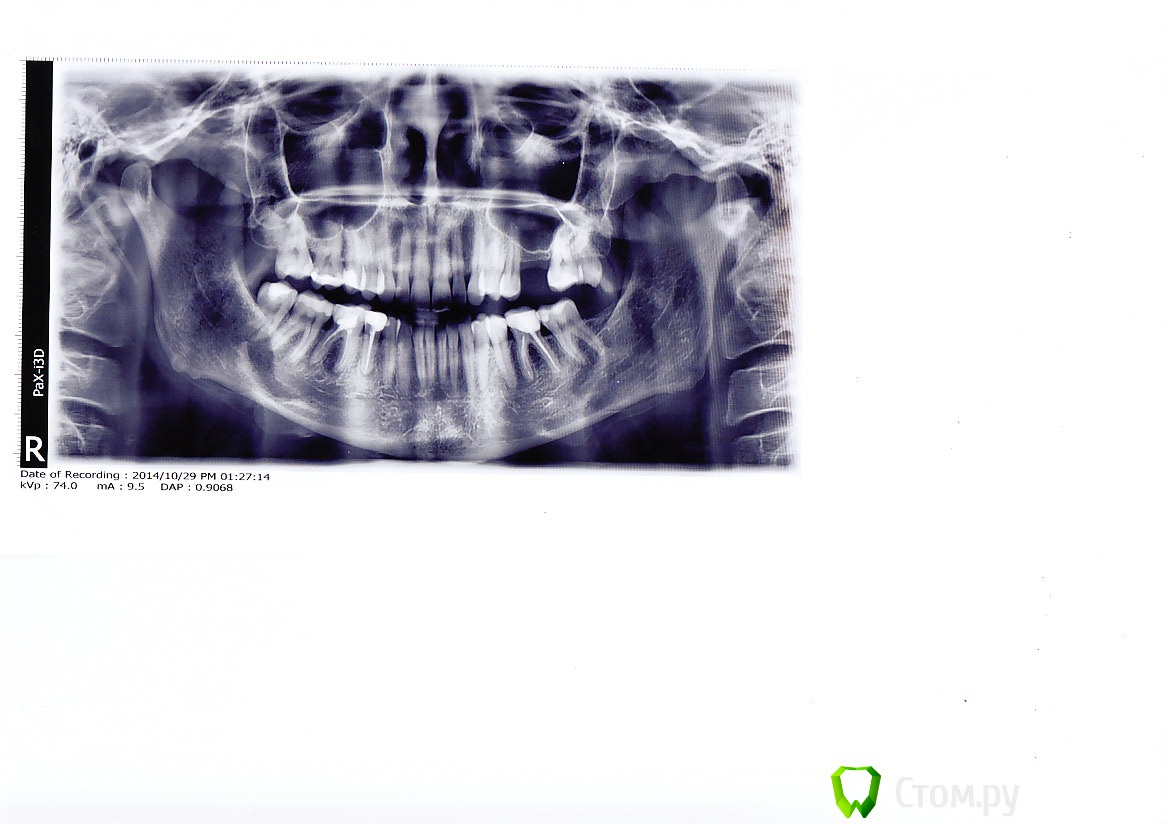

Уважаемые специалисты!Посоветуйте пожалуйста план лечения.Хочу сделать максимально хорошо.Была у нескольких ортопедов и все предлагают разные варианты ,в зависимости от того что они могут предложить.

Можно ли в моем случае установить имплант?Ортопед сказал,что даже если мне нарастят кость,ее будет не достаточно,что бы его нормально поставить.И что  на два зуба стоящих рядом все равно нужно ставить коронки.так как один сильно разрушен,а у второго   отошла десна и он оголился.Какой вариант лучше-мост или имплант?

Еще вопрос,сколько всего нужно поставить коронок?И из какого материала ?

Можно. Необходим синус-лифтинг, возможно понадобится увеличение альвеолярного отростка в ширину.

Почему по вопросу имплантации консультирует ортопед? Должен хирург-имплантолог. Может нет его?

всего необходимо, как минимум, 4 коронки, она из которых - на будущем имплантате. Я думаю, коронки Преттау - наверное лучший вариант для зубов в боковых отделах с разрушение коронковой части зуба ниже уровня десны.

Но! Сначала необходимо перелечивание корневых каналов всех нижних депульпированых зубов (36, 45 и 46)